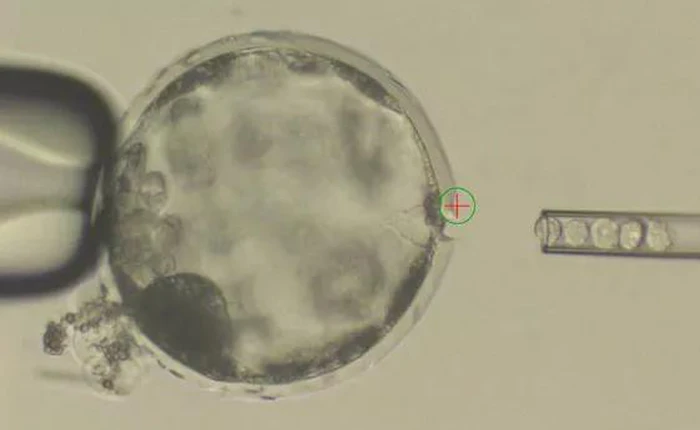

Công nghệ tế bào gốc đã đạt được nhiều thành tựu, ví dụ như các nhà khoa học hiện nay có thể thực hiện nuôi cấy tế bào não bộ siêu nhỏ ngay trong phòng thí nghiệm. Tuy vậy, nó cũng dấy lên nhiều lo ngại về vấn đề đạo đức khi mà ngày càng có nhiều tiến bộ trong việc nuôi cấy tế bào gốc ngay bên trong một cơ thể vật chủ khác.